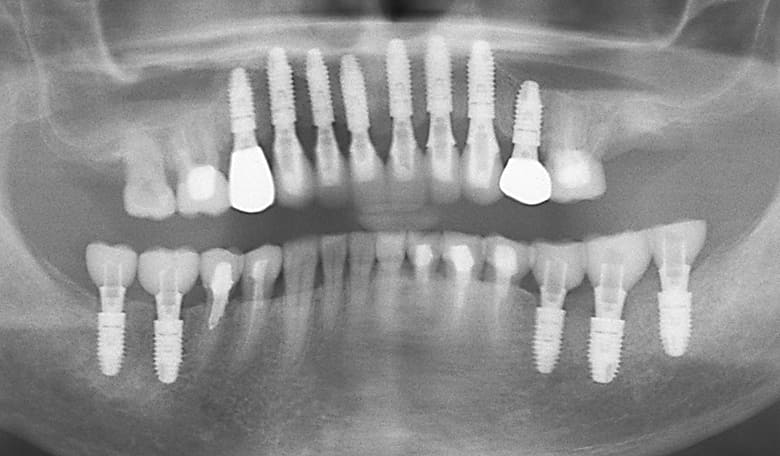

初診時のパノラマX-P所見

#17,15,14,13,23,24,27,36,44,45,46,47 が残根状態で温存は不可能であり、患者さん自身もそれを自覚しておられた。

初診時のパノラマXP所見

上顎前歯を含む第2小臼歯から対側の第2小臼歯までの10本のブリッジが脱離しそれを支えていた歯自体が保存できない状態であった。また下顎の臼歯部も欠損しており、このことで垂直的な咬合の安定が得られず前歯に負担がかかる崩壊脱離したと考えられる。

#15,14,21,22,23,27,36が残根状態で温存は不可能であり、患者さん自身もそれを自覚しておられた。

上顎にインプラント8本を埋入した術後のパノラマXP所見:上顎骨に対するインプラントの長さに関しては12mm-10mmが適切であり前歯部では12mmを小臼歯部では10mmを選択している。また左下のブリッジに関しては温存できなかった第2大臼歯が抜去されている。